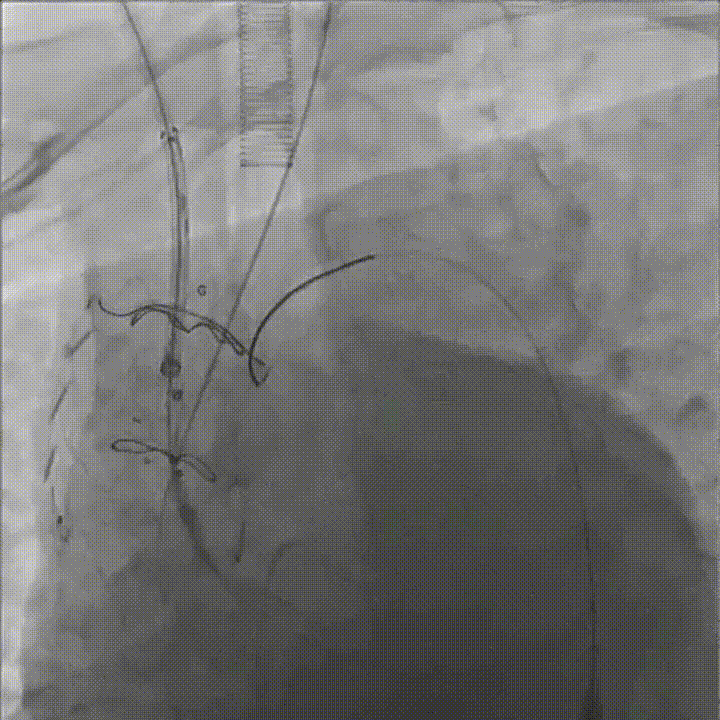

剪除部分覆膜支架及左锁骨下烟囱支架

植入术中单分支支架

术中单分支支架开窗及加固